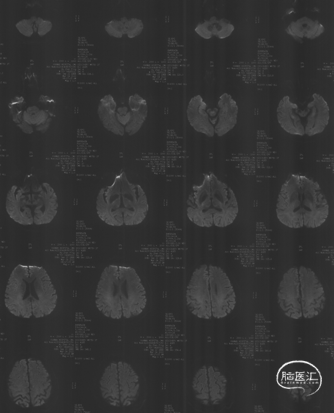

HR-MRI

HR-MRI所见:左椎动脉闭塞段最远到C6横突孔附近。闭塞段近段显示不清,疑似不均匀强化,考虑为斑块;远段信号均匀,平扫为等信号,增强后可见强化,考虑为机化的血栓。